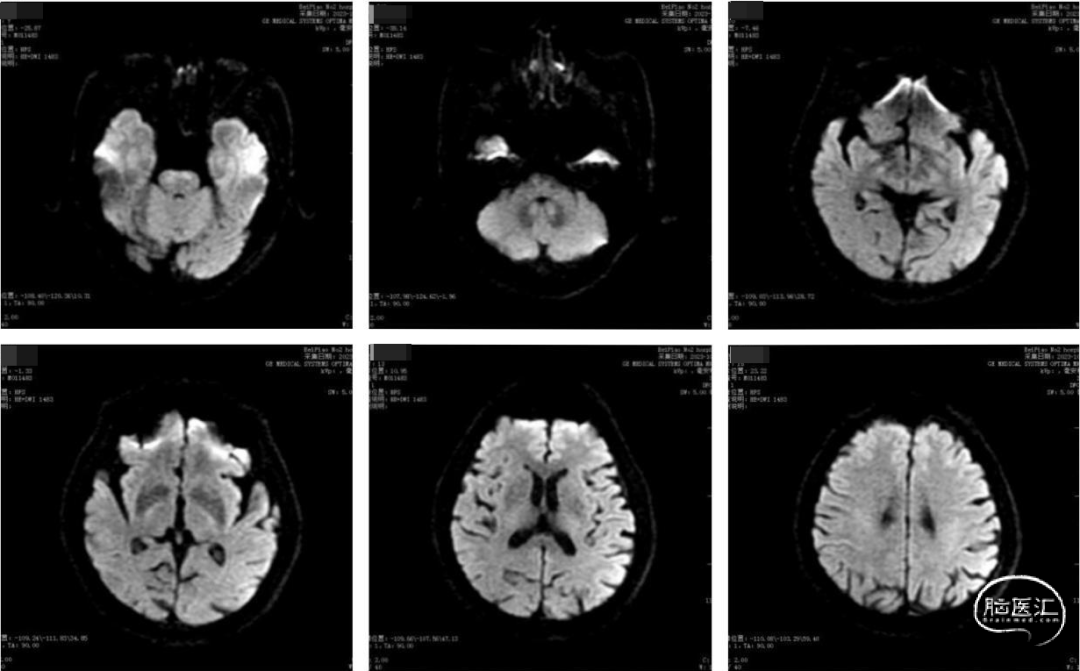

术前影像

术前头部DWI、MRA提示:未见新发脑梗死病灶,右侧椎动脉纤细,左侧椎动脉优势,双侧椎动脉V4段重度狭窄。